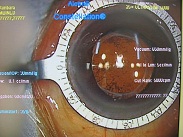

黄斑円孔の手術に関しては、?で記載しましたが、簡単におさらいすると、目の中に器械をいれて、内境界膜という網膜の表層の膜を剥離し、網膜を柔らかくします。その後、目の中に空気を入れてうつ伏せをすることで、円孔の周囲の網膜を浮力で引き寄せて、穴を閉じる。という方法です。